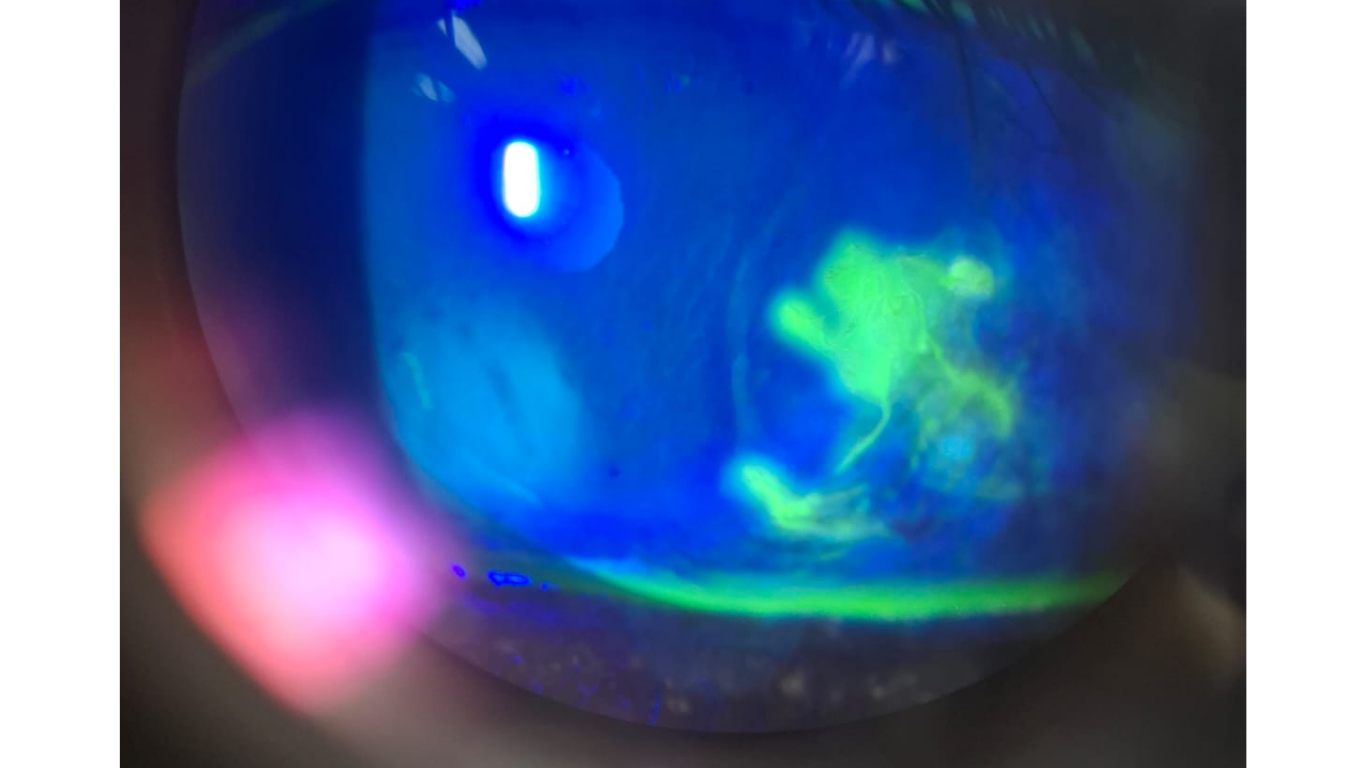

Tragedy on Diwali's First Day: Firecracker Explosion Leaves Two with Severe Eye Injuries